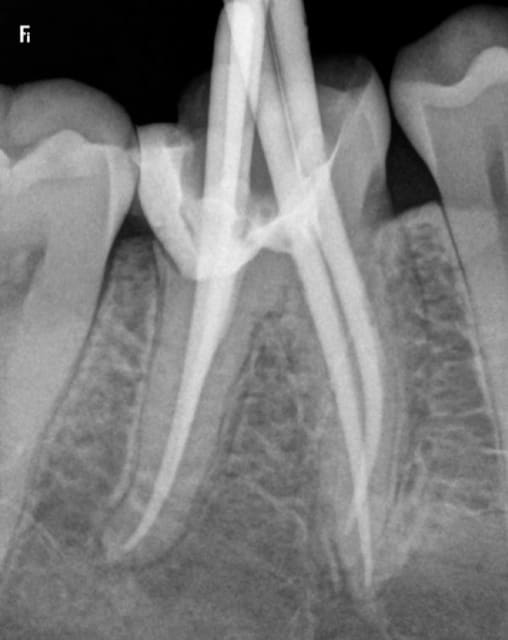

Radio cone en place , cone scellé, cone condensé. Pas de bip intempestif au localisateur d'apex, je vois pas ou j'ai fait une connerie. Pour une fois ou je mets pas la digue ( urgence) . -)

J'ai bien pété une aiguille quick sleeper mais je l'ai enlevée avant . Vous croyez que cette merde a traversé la racine ? C'est curieux quand meme j'ai piqué dans l'espace interdentaire et pas avec une angulation mésio distale. -)

Putain après réflexion je ne vois que ca ! je me disais que la corticale était un peu dure. -)

Ton hypothèse sur le quicksleeper me semble la plus plausible. A faire suivre aux formateurs c'est certes exceptionnelle, mais visiblement ça peut arriver. En tout cas si c'est ça, ca perce bien ce machin là.

Ce qui m'intrigue, c'est qu'une aiguille est beaucoup plus radio opaque (blanc plus franc sur la radio), et en effet, ton axe, chicot, n'est pas celui utilisé habituellement !?!

Ben si mais c'est pas l'axe de l'image que j'ai utilisé. 30 °c'est dans le sens vestibulo lingual pas mésio distal ! Et l'aiguille je l'ai enlevée !-)